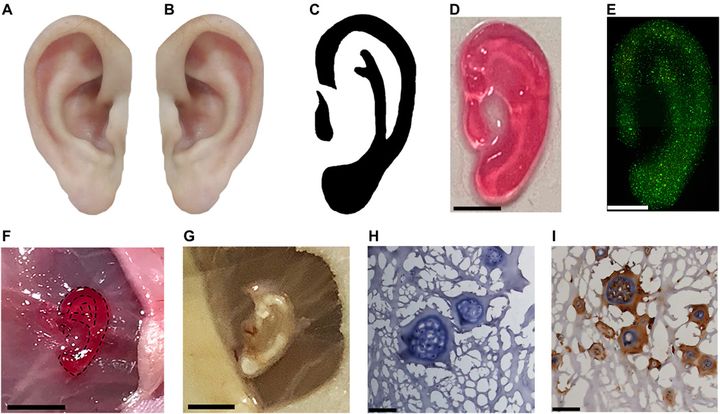

A New Ear, Courtesy of 3D Printing

Charles R. Goulding and Julia Wallace examine the ramifications of the recent announcement of a successful 3D printed ear implant.

3D Printed Ears First Used in Human Patient

In a milestone development, 3DBio Therapeutics have completed reconstruction of a human ear with 3D printing.

Ear-y Developments In 3D Printing And R&D

Charles Goulding Jr. takes a look at bioprinting developments targeting the complex ear.